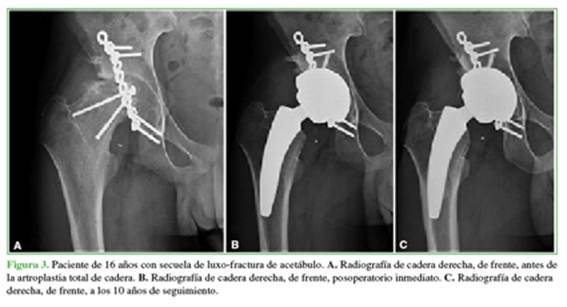

Las causas que llevaron a la indicación de cirugía fueron: tres condrólisis idiopáticas, tres necrosis óseas avasculares (NOA) secundarias a epifisiólisis, dos secuelas de artritis séptica, una secuela de fractura de acetábulo, una displasia del desarrollo con secuela de osteotomía de pelvis fallida y seis casos (las tres bilaterales) de NOA inducidas por tratamiento prolongado de corticoides secundario a enfermedad de Crohn, lupus y leucemia linfoide aguda. En total, nueve (56%) de los casos corresponden a NOA secundaria a diferentes causas (Tabla 2, Figura 2). Ocho (50%) tenían cirugías previas a la ATC (Figura 3).

Se registró una complicación en un paciente de 20 años operado por secuela de artritis séptica en la infancia. En el momento de la cirugía, tenía una agenesia casi completa de la cabeza femoral con un acetábulo displásico y un acortamiento de miembro de 35 mm. En el acto quirúrgico, se produjo una fractura de trocánter mayor tratada con lazadas de alambre y, en el posoperatorio, cursó con parálisis motora del nervio ciático y dolor neuropático. A los seis meses de la ATC, requirió una neurólisis del ciático. Al final del seguimiento, la recuperación de la función motora era completa, no tenía renguera, pero sufría un dolor neuropático persistente, con disestesias en la planta del pie.